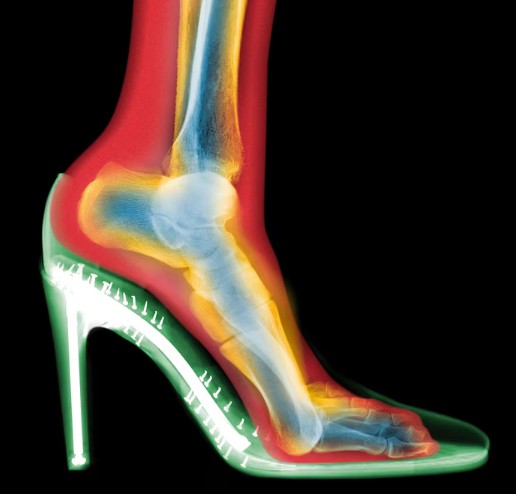

Colored MRI-style X-ray shows a stiletto shoe elevating the heel and forcing the foot into a downward angle. This altered position shifts body weight forward, changing gait mechanics and increasing strain on the knees, hips, and lower back. (Photo By Nick Veasey, Science Photo Library)